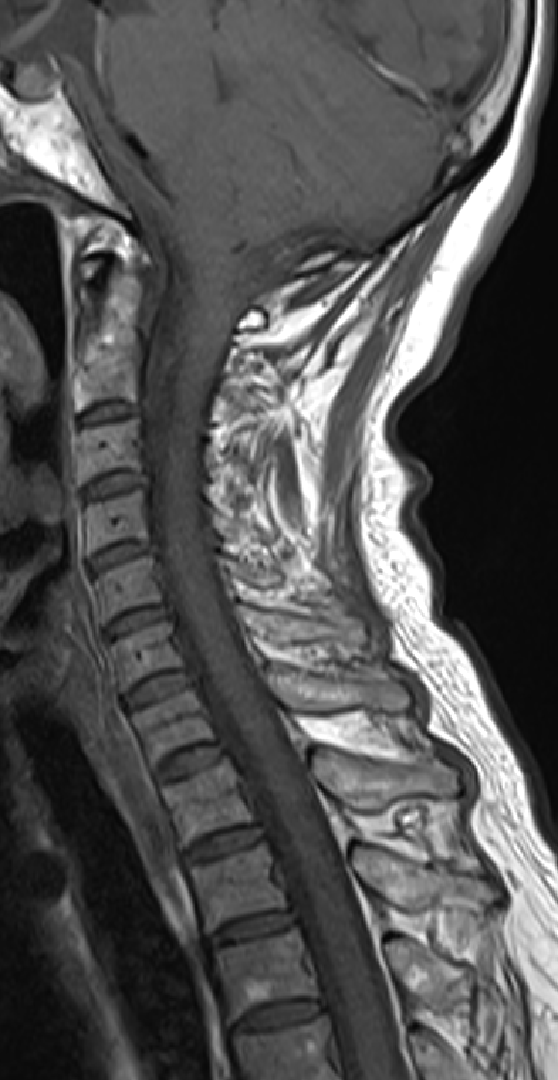

2013-5-16 MRI

2013-5-16